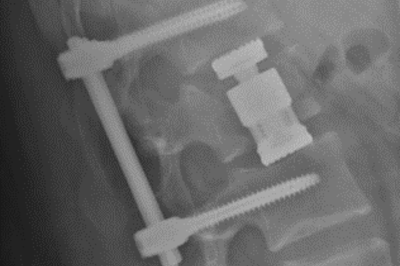

• Verschraubter Wirbelbruch

Röntgenbild verschraubter Wirbelbruch. Seitliche Ansicht

Versorgung mit Schrauben-Stab-System und Ersatz des Bandscheibenfaches